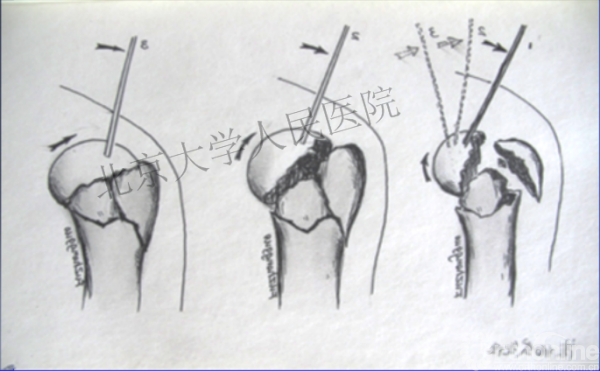

克氏针的应用“joystick”

简单骨折的闭合复位技术:以克氏针作为“joystick”

髓内钉的应用复位是关键